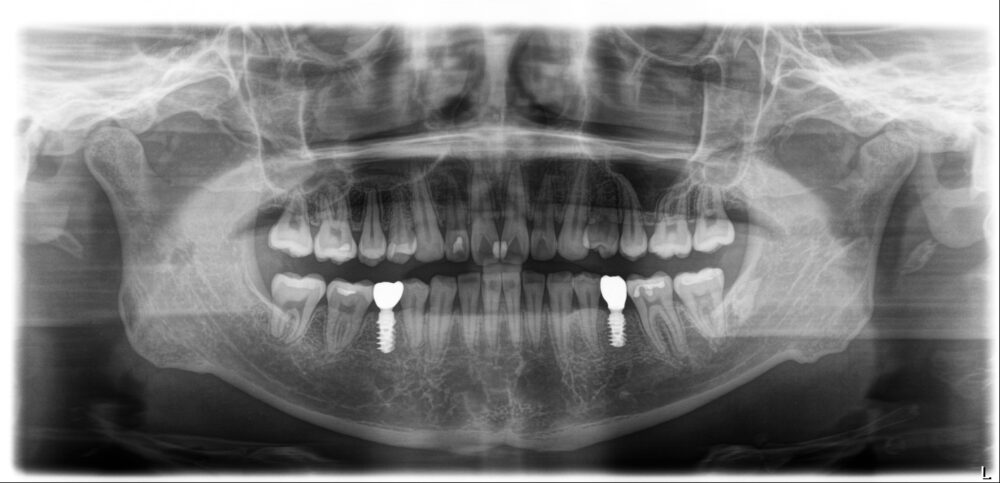

矯正治療開始より1年10ヵ月後、両側下の5番目にインプラントOpeを行い、3ヵ月後プロビジョナルレストレーション(暫間修復歯)を入れることになりました。

治療再開から6ヵ月、奥歯8本に予定していた補綴治療(セラミックの詰め物や被せ物)を行い、治療終了です。

治療前気になっていた「出っ歯」が気にならなくなり、治療前は歯が抜けていない方ばかりを使っていた片方噛みをしなくなったと審美的にも機能的にも仕上がりを喜んでおられます。

治療期間 3年3か月(プレオルソ・アライナー・ブラケット)